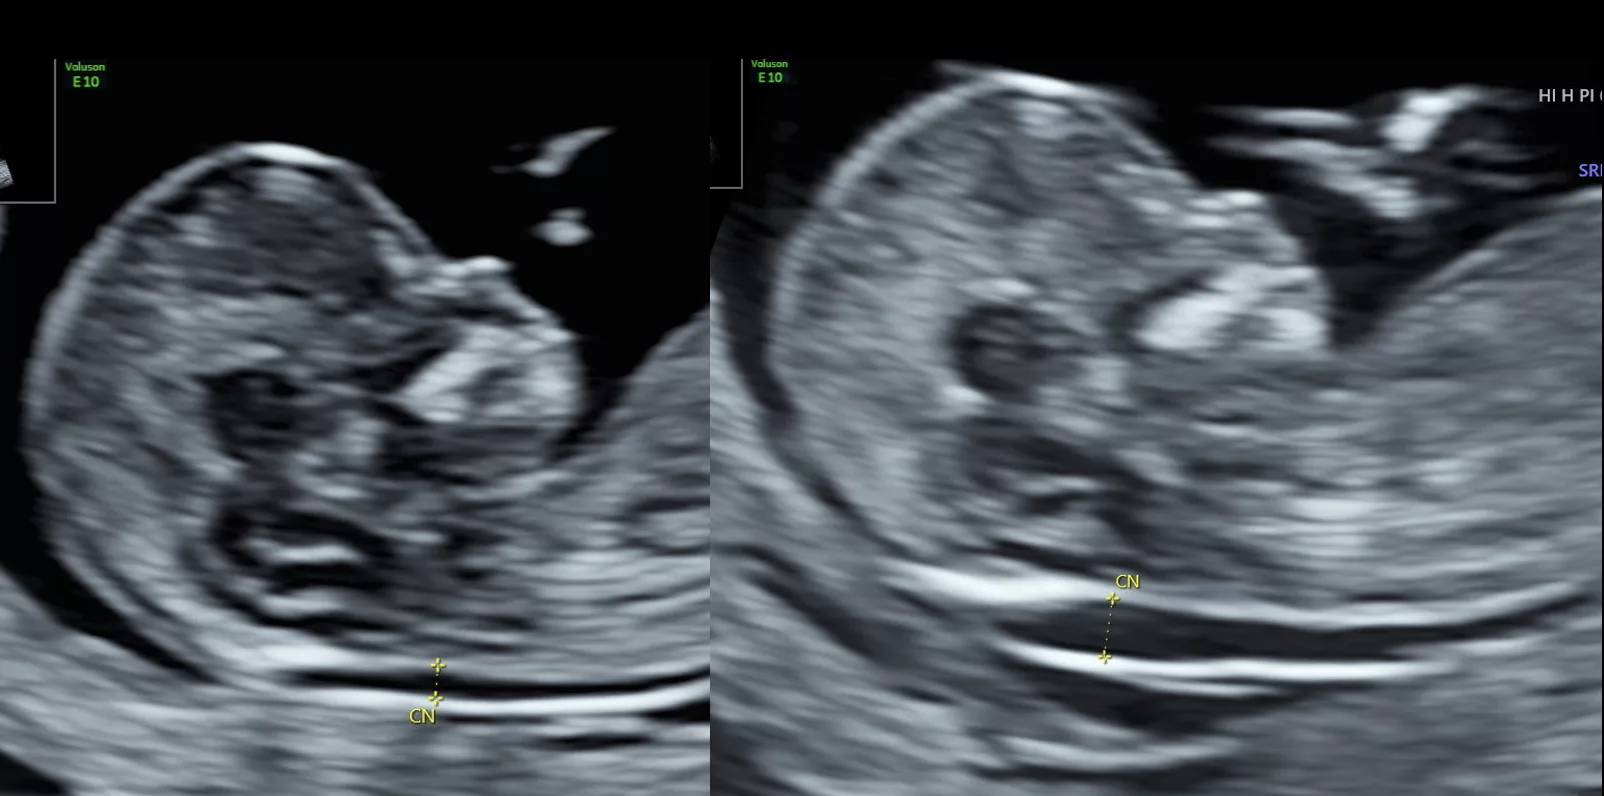

Contrôle Qualité & Agrément

Les praticiens du centre réalisant des échographies obstétricales sont soumis à un contrôle de qualité annuel et possèdent un agrément pour la mesure de la clarté nucale de l’échographie du 1ᵉʳ trimestre, dans le cadre du dépistage de la trisomie 21.